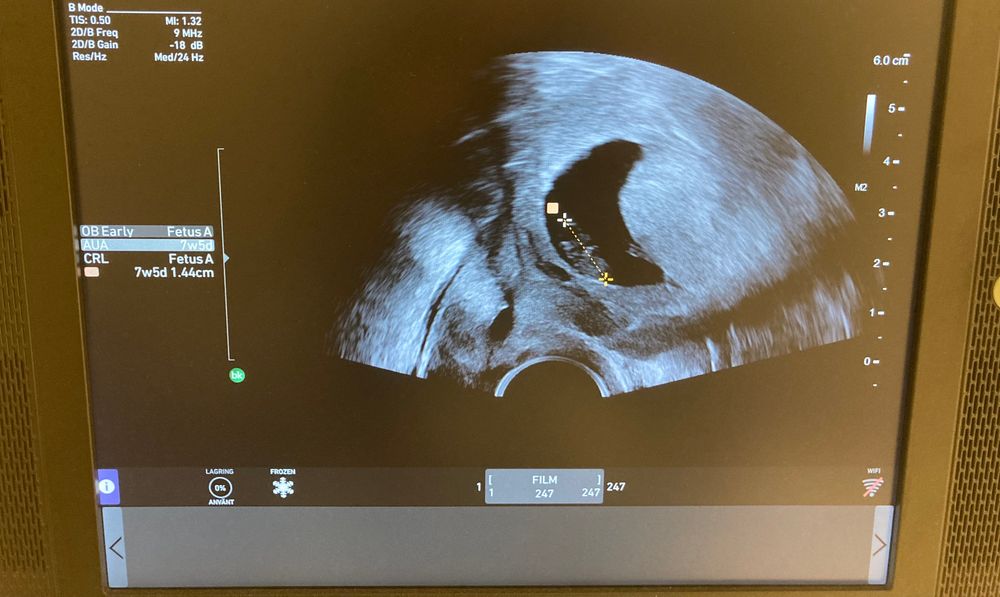

Olga S в Благополучная беременность 2 года по какой стенке прикрепление? УЗИ, КТГ, доплер кто понимает - по какой стенке прикрепление - передней или задней? забыла спросить на узи. Посмотрите еще 20 записей на эту тему Отменить Ответить Дашута Никто, кроме врача, который делает УЗИ СЕЙЧАС, вам не скажет. Положения датчика могут быть разные. О таком нужно спрашивать по факту, ну либо гадать 26.06.2023 Ответить Оленька А по узи можно определить? Самой интересно🧐 я имею ввиду не узисту или доктору 26.06.2023 Ответить Как часто делали узи во время беременности? Ретрохориальная гематома Чаты Беременных Выберите чат: Январята-2026 Февралята-2026 Мартята-2026 Апрелята-2026 Майчата-2026 Июнята-2026 Июлята-2026 Августята-2026